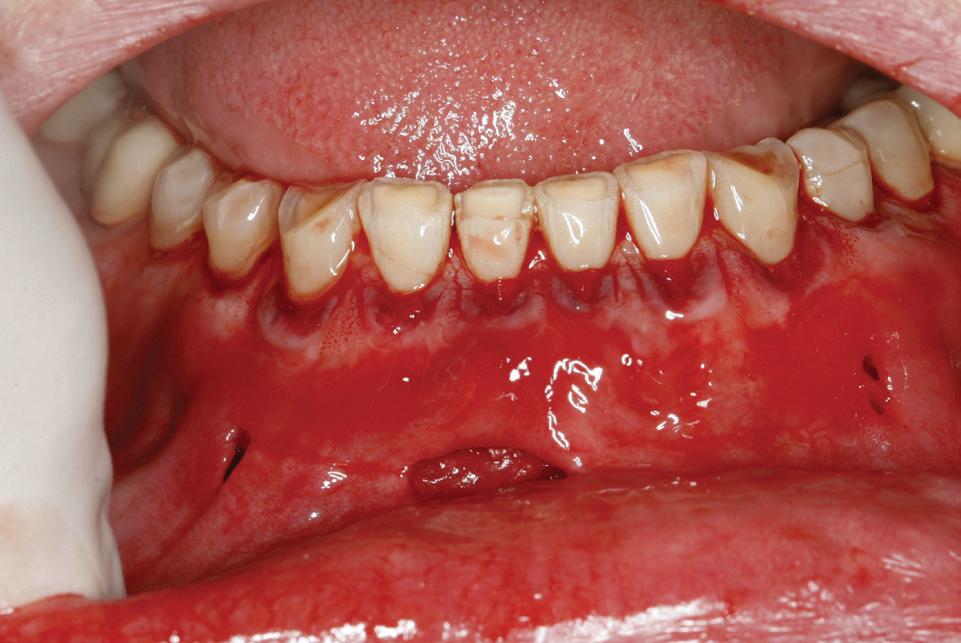

Lamboul repoziționat apical

Această tehnică este o opțiune atunci când nu există suficient țesut gingival keratinizat și este preferată atunci când caninul impactat este situat mezial față de incisivul lateral. Lamboul trebuie fixat și adaptat la dinte. Dezavantajele includ riscul de recesie și marginea gingivală neregulată, alături de necesitatea unei intervenții chirurgicale osoase extinse. Se efectuează incizii verticale, iar lamboul este deplasat într-o direcție laterală sau apicală. Se recomandă un design al lamboului în care baza și zona coronară sunt fie la aceeași lățime, fie mai înguste la bază, cu o grosime de 4-5 mm, astfel încât lamboul să fie suficient de lat meziodistal, extinzându-se cu 1,5 mm dincolo de unghiul dintelui (fig. 6, 7).

Osul acoperitor trebuie îndepărtat cu chiuretă sau freză diamantată pentru a expune porțiunea liberă a coroanei. Lamboul se poziționează apoi la CEJ și se fixează cu suturi periostale pentru o stabilitate mai mare. În funcție de gradul de impactare a caninului, se poate plasa un pansament parodontal, astfel încât țesutul să nu se închidă. Bracketul este plasat fie în momentul procedurii, fie la 10 zile postoperator. Dacă respectivul canin este situat prea apical, se preferă tehnica închi-

să. În general, deplasarea ortodontică începe la 4-6 săptămâni după expunerea chirurgicală. Când foliculul ce înconjoară caninul este larg, incizia lamboului trebuie făcută peste limitele acestuia, pentru a permite adaptarea optimă a lamboului la coroană și os. Pentru a determina buna adaptare a lamboului, atunci când buza se mobilizează, acesta ar trebui să rămână staționar.

Figurile: 4. Accesoriu de tipul porții batante utilizat pentru tracționarea directă a unui canin palatinal gestionat cu expunere deschisă.

5. Expunerea deschisă a unui canin cu impactare palatinală; s-a utilizat o bară transpalatinală ca sursă de ancorare cu un braț extensibil conceput pentru tracțiune directă.

6, 7. Utilizarea lamboului repoziționat apical pentru a gestiona caninii bilaterali cu impactare facială. După expunere, s-a practicat și frenectomia și au fost plasate bracketuri bilaterale (fig. 6). S-a realizat tracțiunea ortodontică, ce a permis poziționarea corespunzătoare a ambilor canini pe arcada superioară (fig. 7)

apoi direcționarea vestibulară a caninului (fig. 8, 9).